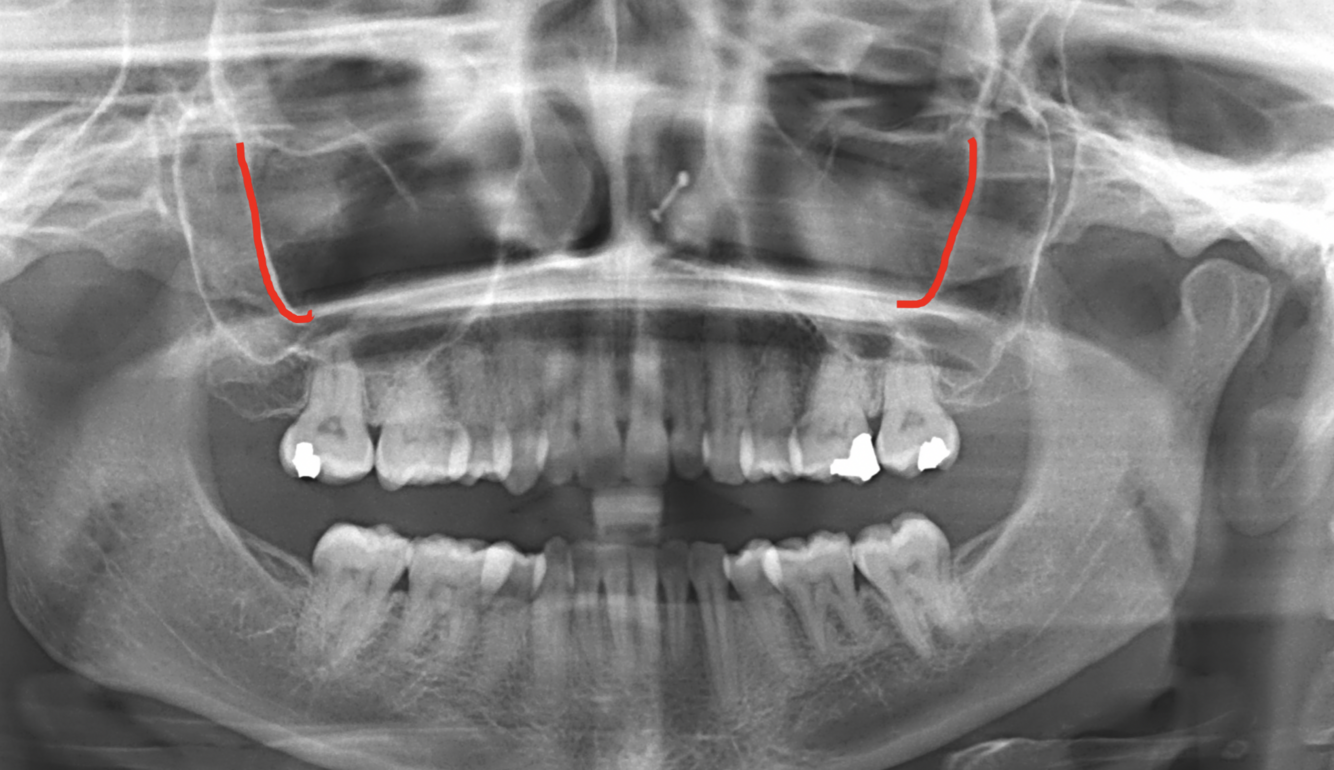

What does the red indicate in the following image?

Signmoid notch